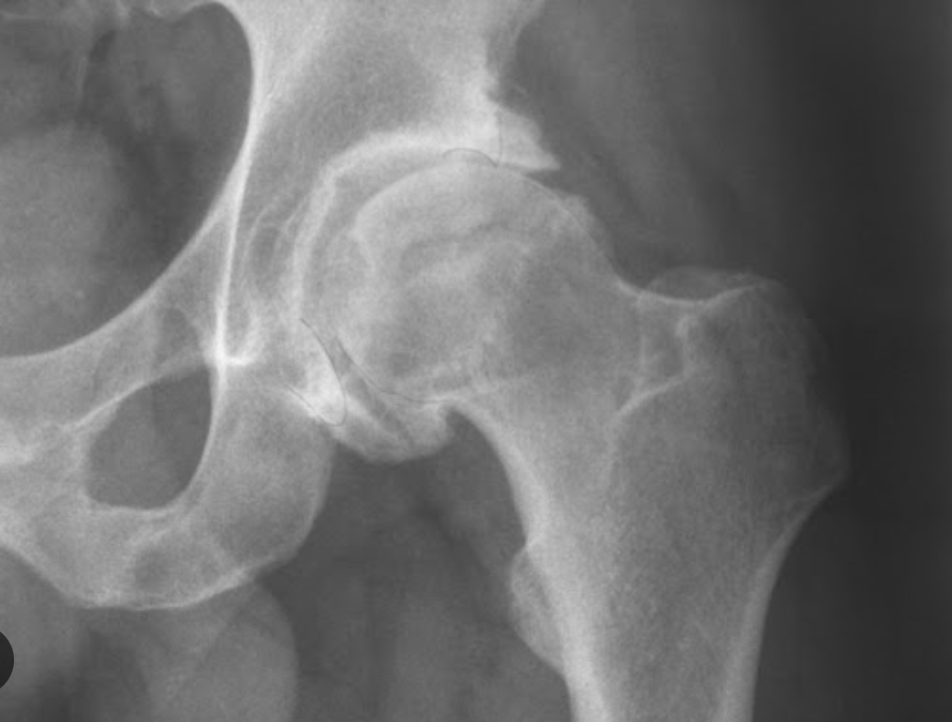

Datos de coxartrosis Rx

Disminución del espacio articular

Osteofitos

Esclerosis subcondral

Quistes subcontrates (geodas)

Deformidad

Coxartrosis